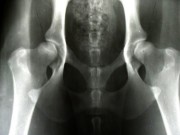

Příklady vyhodnocení DKK

kloubní štěrbiny symetrické, úzké, hlavice hluboko uvnitř jamek, středy hlavic více než 2 mm za okrajem jamky, hlavice kulovité, krček dobře ohraničený, přední okraje kyčelních jamek úzké, ostře ohraničené, Norbergův úhel 110 stupňů, žádné znaky artrózy.

kloubní štěrbiny mírně nesymetrické, úzké, středy hlavic těsně uvnitř za okrajem jamky, hlavice kulovité, přední okraj jamek mírně zesílený, bez znaků artrózy, Norbergův úhel 107 stupňů.

kloubní štěrbiny nesymetrické, rozšířené, středy hlavic těsně vně okrajů jamky, hlavice mírně oploštělé, patrné zesílení v úponu kloubního pouzdra, tzv. Meduza linie, přední okraje jamek zesílené, počínající artróza, Norbergův úhel 102 stupňů.

obě kloubní štěrbiny silně nesymetrické, rozšířené, středy hlavic vně okrajů jamky, hlavice oploštělé, krčky zkrácené, přední okraje jamek velice zesílené, opotřebené, vlevo středně, vpravo mírně pokročilé artrózní změny, Norbergův úhel 92 stupňů.

kloubní štěrbiny zcela nesymetrické, středy hlavic daleko vně okraje hlavic, hlavice zcela deformované, krček neohraničitelný, silná artróza s rozsáhlou tvorbou výrůstků, Norbergův úhel pod 90 stupňů.

vlevo kloubní štěrbina zcela nesymetrická, široká, střed hlavice daleko vně za okrajem jamky, přední okraj jamky zcela opotřebený, hlavice silně deformovaná, hřibovitá, krček zkrácený, zesílený a těžko ohraničitelný, Norbergův úhel méně než 90 stupňů, pokročilá artróza, vpravo kloubní štěrbina ve vnější třetině divergentní, střed hlavice 1 mm uvnitř za okrajem jamky, hlavice kulovitá, přední okraj jamky ve vnější části mírně šikmý, zesílený, Norbergův úhel 105 stupňů.

vlevo kloubní štěrbina zcela nesymetrická, široká, střed hlavice daleko vně za okrajem jamky, přední okraj jamky zcela opotřebený, hlavice silně deformovaná, hřibovitá, krček zkrácený, zesílený a těžko ohraničitelný, Norbergův úhel méně než 90 stupňů, pokročilá artróza, vpravo kloubní štěrbina mírně nesymetrická, rozšířená, střed hlavice přímo na okraji jamky, hlavice se znatelným zesílením v oblasti úponu kloubního pouzdra - tzv. Meduza linie, přední okraj jamky zesílený, počínající artróza, Norbergův úhel 105 stupňů.